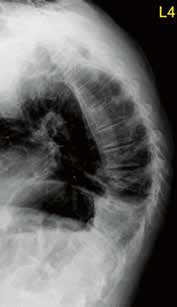

Osteoporotische Sinterungsfrakturen treten in Deutschland mit zunehmender Häufigkeit auf. Vergesellschaftet damit sind eine erhöhte Morbidität und Mortalität. Die epidemiologischen Daten dazu zeigen klar die daraus resultierenden Probleme wie einen erhöhten Medikamentenbedarf, vermehrte Krankenhausaufenthalte, Depression, soziale Isolierung und eine erhöhte 5‑Jahres-Mortalität. Frakturen und daraus resultierende Fehlstellungen begünstigen Anschlussfrakturen. Eine Abhängigkeit von der Knochendichte besteht insofern, als niedrige Werte im T‑Score das Risiko verstärken. Kyphoseassoziierte Fehlstellungen scheinen das Risiko ebenso zu erhöhen. Osteoporosebedingte Gestaltveränderungen gelten heute als häufigste Ursache relevanter adulter Deformitäten der Wirbelsäule (Abb. 1) 1 2.